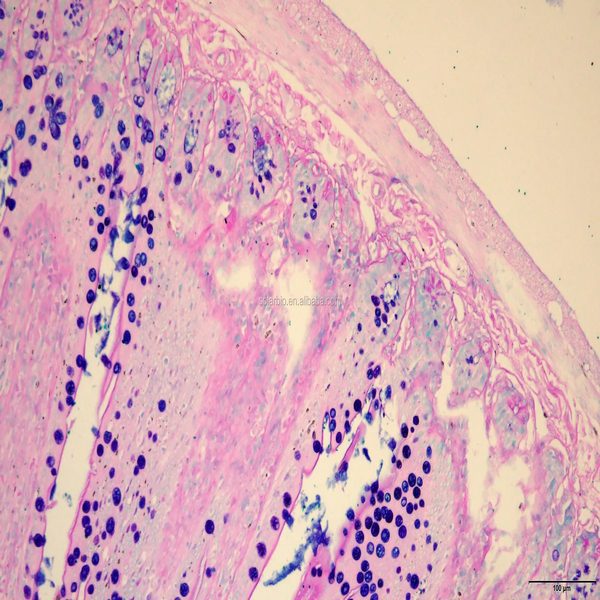

- General and specialized tissue and cell staining

- Prepare educational slides for students from all available tissues

Histological methods includes sample processing in the pathology laboratory, preparation of the slide and its examination under a microscope, sample fixation, molding, microtome cutting, staining and assembly of the slides.